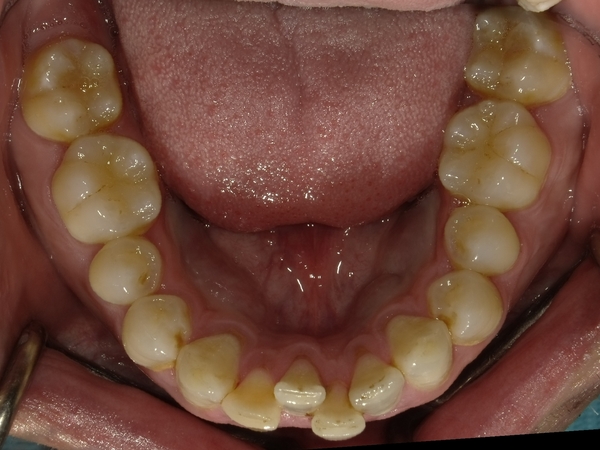

ガタガタとした歯並びや八重歯(叢生)CASE74